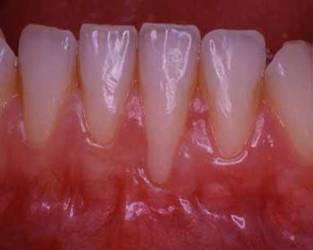

Superfici radicolari esposte derivano da recessioni gengivali. E' possibile migliorare il suo sorriso coprendo una o più di queste radici che fanno apparire il dente più lungo. E' altrettanto possibile ridurre la sensibilità delle radici esposte all'introduzione di cibi o liquidi, caldi o freddi.

Recessione gengivale ed esposizione della radice |